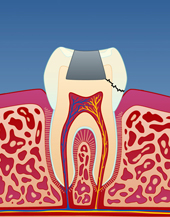

Bildet viser en jeksel i underkjeven med en stor amalgamfylling. Det går en tydelig bruddlinje langs den ene tyggeknuten.

![]()